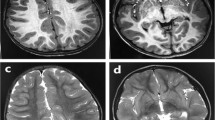

The ubiquitin–proteasome system is the principal system for protein degradation mediated by ubiquitination and is involved in various cellular processes. Cullin-RING ligases (CRL) are one class of E3 ubiquitin ligases that mediate polyubiquitination of specific target proteins, leading to decomposition of the substrate. Cullin 3 (CUL3) is a member of the Cullin family proteins, which act as scaffolds of CRL. Here we describe three cases of global developmental delays, with or without epilepsy, who had de novo CUL3 variants. One missense variant c.854T>C, p.(Val285Ala) and two frameshift variants c.137delG, p.(Arg46Leufs*32) and c.1239del, p.(Asp413Glufs*42) were identified by whole-exome sequencing. The Val285 residue located in the Cullin N-terminal domain and p.Val285Ala CUL3 mutant showed significantly weaker interactions to the BTB domain proteins than wild-type CUL3. Our findings suggest that de novo CUL3 variants may cause structural instability of the CRL complex and impairment of the ubiquitin–proteasome system, leading to diverse neuropsychiatric disorders.

Nakashima, M., Kato, M., Matsukura, M. et al. De novo variants in CUL3 are associated with global developmental delays with or without infantile spasms. J Hum Genet 65, 727–734 (2020). https://doi.org/10.1038/s10038-020-0758-2